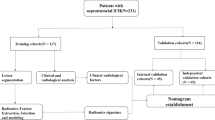

Consecutive patients with mild, moderate, or severe brain contusion were included in the analysis. Inclusion criteria were: (1) baseline computed tomography (CT) showing intraparenchymal bleeding and (2) record of a baseline CT scan and a follow-up CT after primary brain contusion. Exclusion criteria were: (1) less than 18 years old; (2) a documentation of the baseline CT scan over 6 h or a follow-up CT undertaken within 48 h following brain injury; (3) underwent surgery prior to the follow-up CT scan; (4) initial blood evaluation test over 24 h of occurrence of the injury; (5) history of head trauma, stroke, or brain tumor; and (6) history of anticoagulant use prior to cerebral contusion (Fig. 1).

Flowchart illustrating the selection of patients based on the inclusion and exclusion criteria. a Patients in the development dataset were selected from the First Affiliated Hospital of Shantou University Medical College, the Second Affiliated Hospital of Shantou University Medical College, and the Affiliated Jieyang Hospital of Sun Yat-sen University between May 2012 and June 2018. b Patients in the external validation dataset were selected from the Affiliated East Hospital of Xiamen University between March 2014 and June 2019. CT non-contrast computed tomography

A total of 889 patients with tICH expansion were included in the development dataset (Fig. 1; Table 1). Among them, 487 (55.22%) patients had a mild GCS level (13–15 score) at admission, and 779 (88.73%) brain contusions occurred in the frontal and temporal lobes. The ICC was 0.812, suggesting a good agreement between automatic volume calculation with and without fine-tuning. Among these individuals with brain contusion, 198 (22.27%) had significant acute tICH expansion, and 47 (5.29%) died in hospital. Compared with the patients without tICH expansion, those with tICH expansion had a higher rate of in-hospital mortality. In terms of clinical variables, individuals with acute tICH expansion had relatively high mean arterial pressure, MLR, and frequency of hypertension, coagulopathy, and diabetes, and a severe or moderate GCS level on admission. In terms of imaging variables, individuals with acute tICH expansion had a relatively large baseline tICH volume, short time from brain trauma to initial CT scan, and a high frequency of subarachnoid hemorrhage, subdural hemorrhage, and multihematoma fuzzy sign.

TPHEA Nomogram Validation